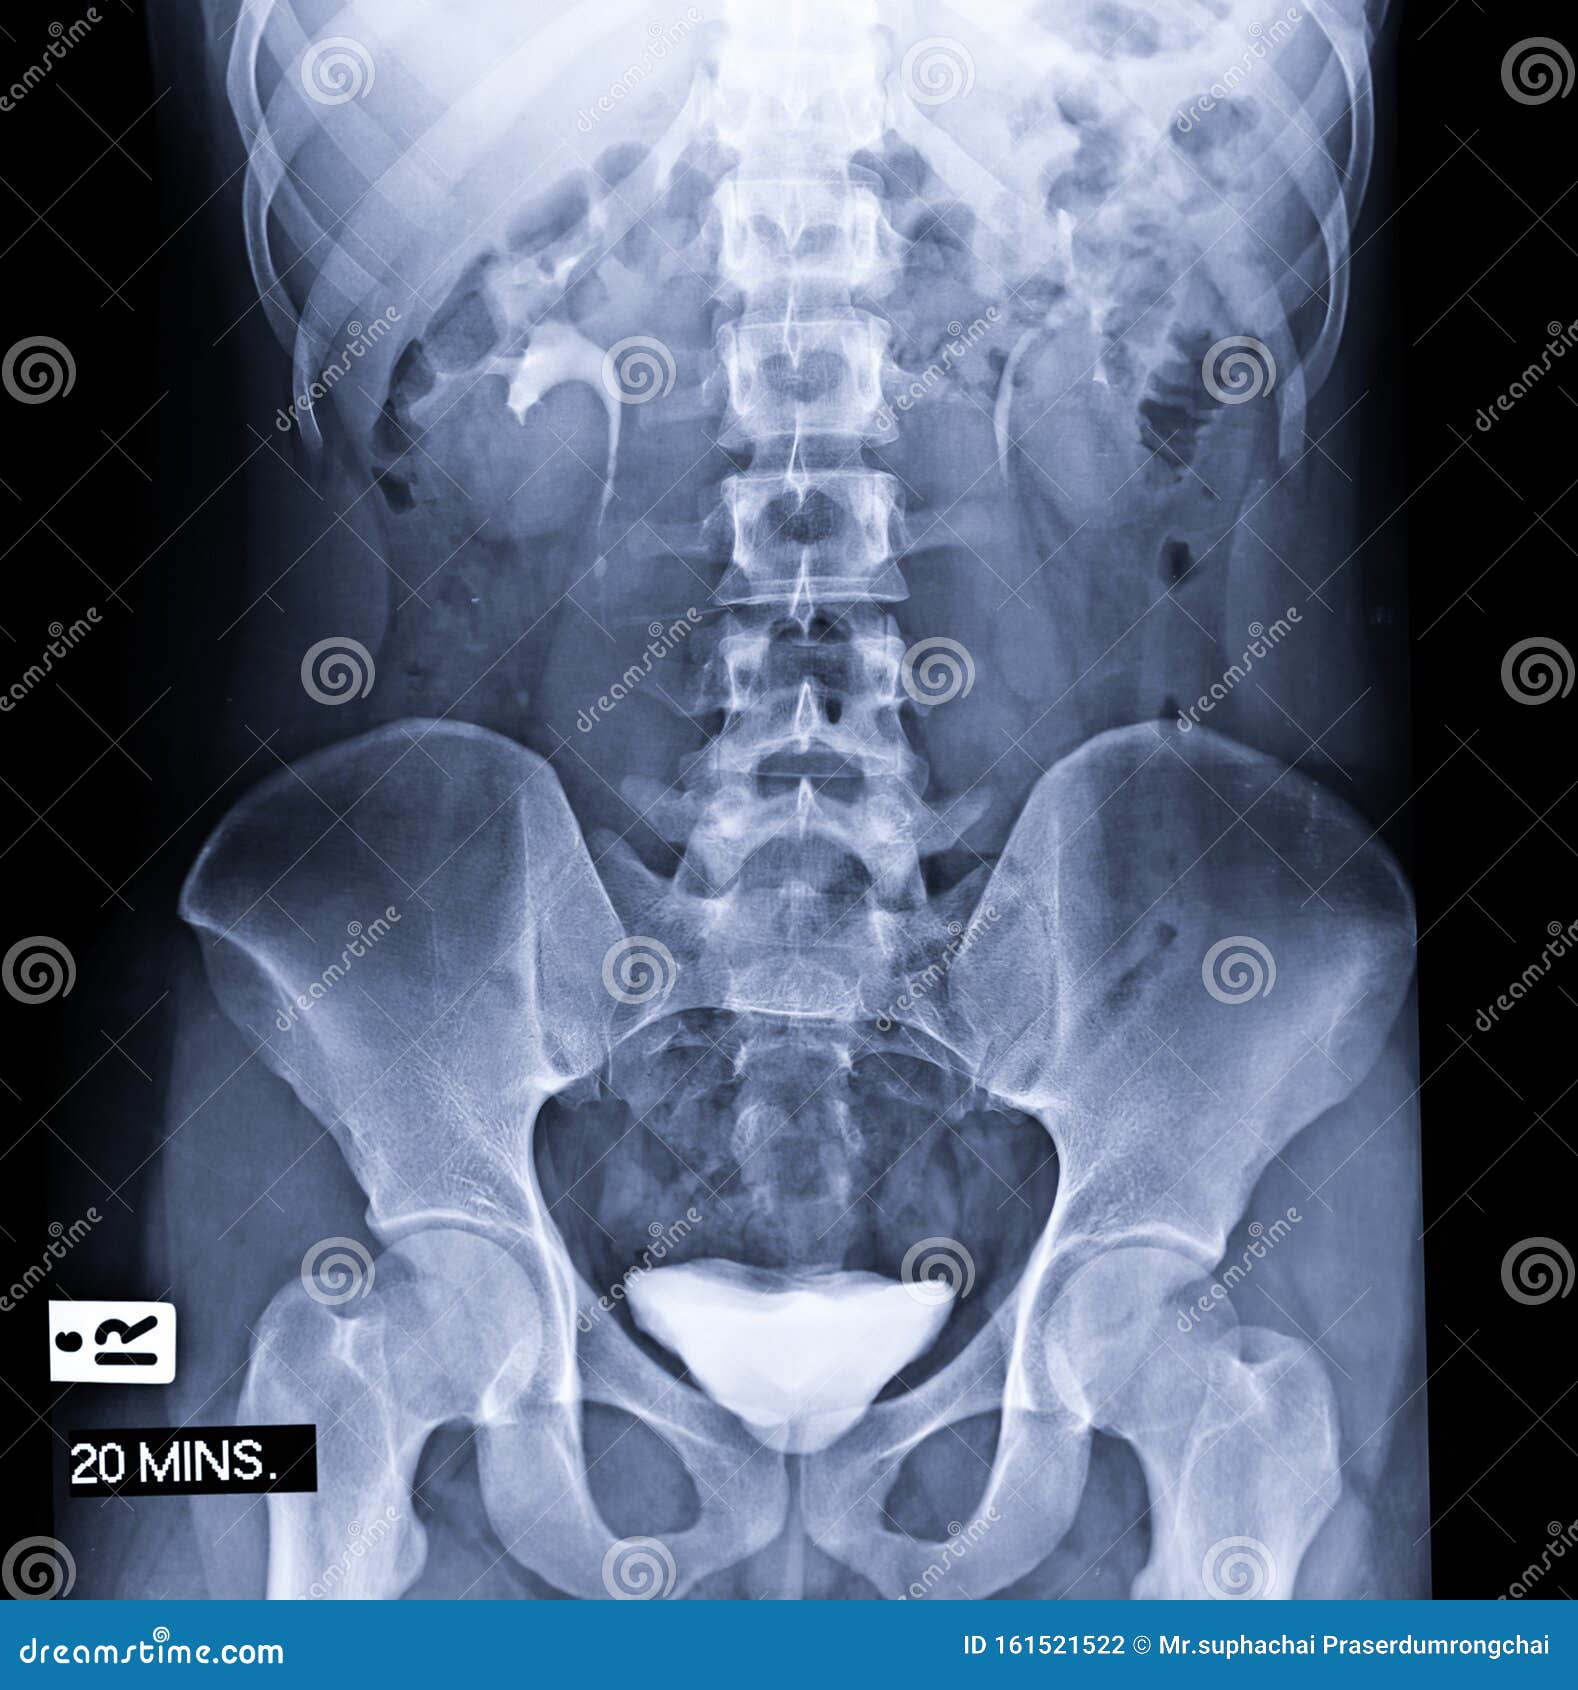

Supine Position Of Urinary Tract Xray Image Stock Photo – Download …

Plain Kub Or Xray Image Of Urinary System Showing Kidney And Bladder …

Radiographic Anatomy – Abdomen AP Supine IVP | Radiology student …